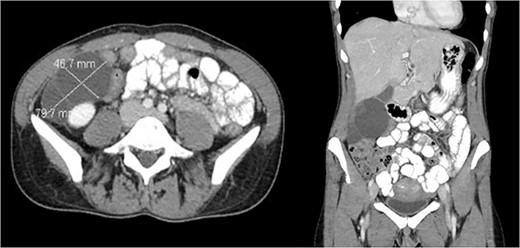

A 47-year-old female with no significant past medical history presented with right lower quadrant pain radiating to the back, which had persisted for 3 days. Additionally, she reported a 6 pound weight loss over the course of one year. She had no personal or family history of malignancy. Her labs were within normal limits and her CEA, CA 19–9, CA 125, and CA 27.29 were not elevated. A CT scan of the abdomen and pelvis (Fig. 1) revealed a multilobulated, multiseptated, well circumscribed cystic mass measuring 8.0 × 4.7 × 7.9 cm in size abutting the inferior aspect of the gallbladder extending anteriorly to the right kidney into the paracolic gutter. Ultrasound imaging (Fig. 2) revealed as multiseptated cystic mass measuring 4.4 × 7.7 × 9.3 cm, suspicious for exophytic complex hepatic cyst. No mural nodularity or abnormal mural hypervascularity was seen. Tumor markers LDH, CA 125, and CEA were within normal limits. The decision was made to perform a diagnostic laparoscopy with potential resection.

CT showing cystic structure abutting the right kidney, liver, and gallbladder.